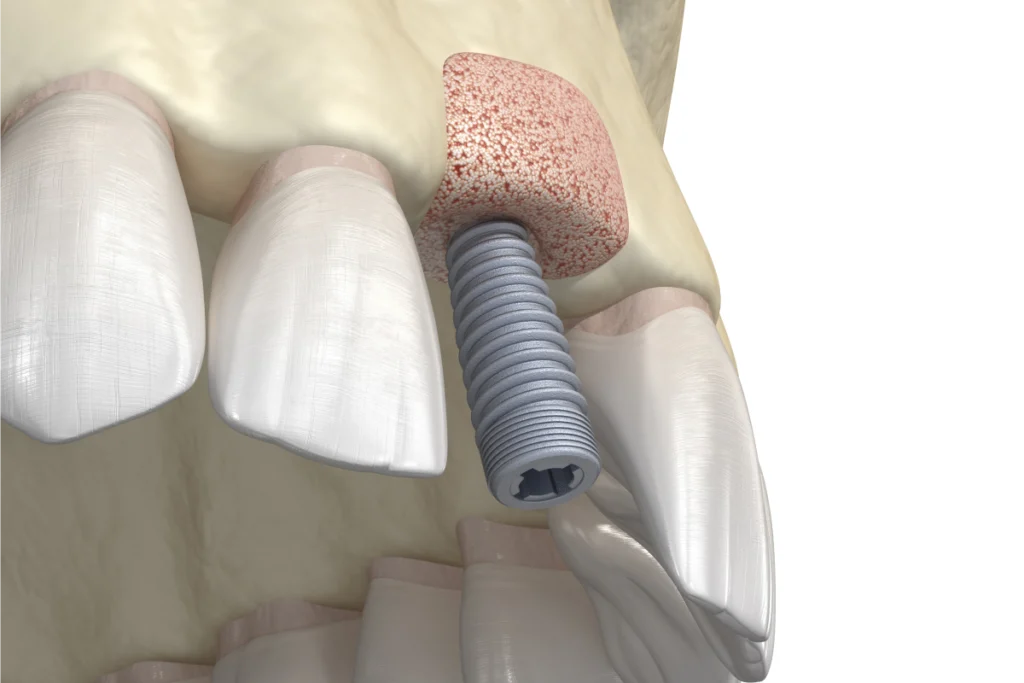

Implants dentaires

Les implants dentaires permettent de remplacer une ou plusieurs dents manquantes de manière durable.